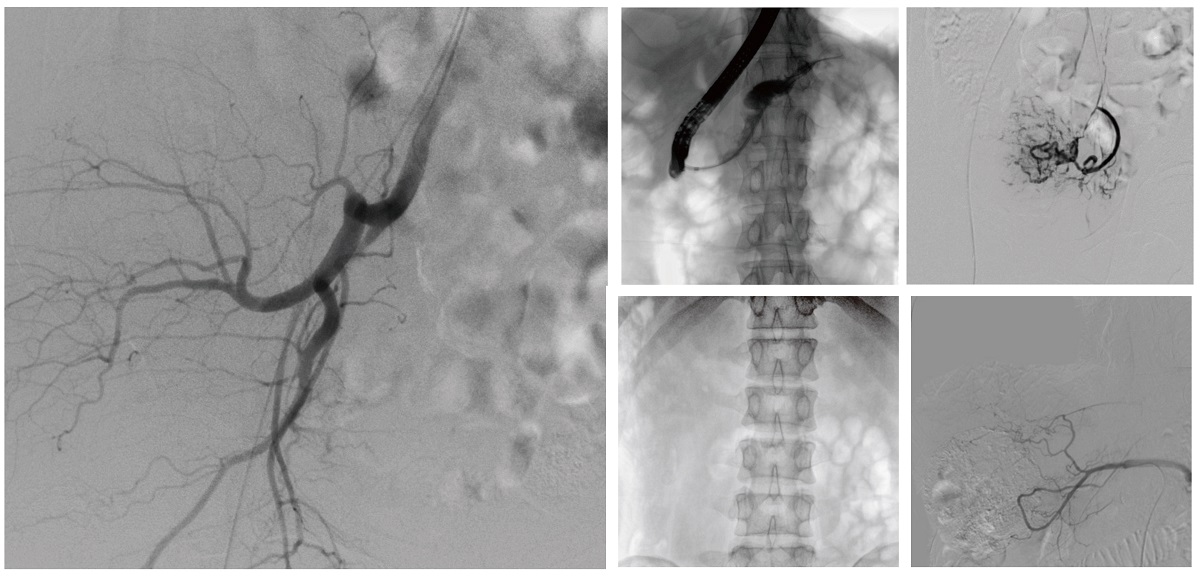

醫(yī)院引進(jìn)的普愛醫(yī)療移動(dòng)式平板介入中C,其高清成像能力覆蓋骨科、介入科、泌尿外科、婦產(chǎn)科等多科室,能夠滿足介入微創(chuàng)手術(shù)的多樣化需求。

設(shè)備的移動(dòng)式設(shè)計(jì),無(wú)需對(duì)現(xiàn)有手術(shù)室進(jìn)行改造,適合高負(fù)荷手術(shù)量或應(yīng)急情況下的靈活部署。如在急診介入手術(shù)中,該設(shè)備能迅速響應(yīng)需求,為醫(yī)生提供實(shí)時(shí)影像支持,提升搶救效率。